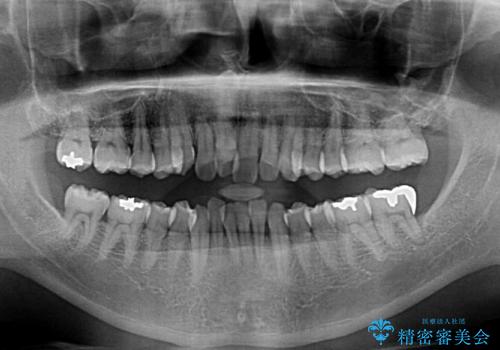

前歯のデコボコ ワイヤー装置での短期間治療

- 前歯のデコボコを気にして来院された患者様です。

インビザラインまたはワイヤー装置、どちらでも対応可能でしたが、自己管理の少なさ、期間の短さから、ワイヤー装置による矯正治療を行うこととしました。

治療開始の頃は、食事や歯磨きが慣れず、装置が頻繁に脱落しましたが、2,3ヶ月ほどで慣れ、その後は1年ほどで治療を終えることができました。